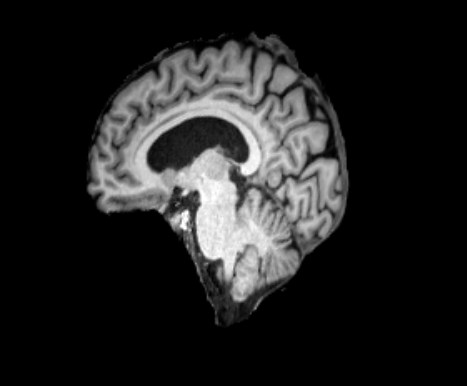

3.2.2 Robustness

In this experiment, we evaluate the robustness of Polaffini and the competing methods by computing a failure rate. We considered as potential outliers all cases for which the average Dice score over all regions after registration was below 0.34 (Z-score below -1.5, pooling Dices from all affine methods). All potential outliers were visually inspected to assess the reason behind the poor anatomical structure overlap score. All of them were clear failure cases, not just a residual misalignment to be expected after an affine registration. The failure counts for each method are reported in table 2. Almost all of the failure cases only occurred when registering with Flirt, mostly when subjects from the IXI dataset were involved. The most common failure type, showcased in Fig 6-a., consists of a local minimum where the frontal part of the moving brain is matched with the cerebellum of the reference one, a less frequent upside-down outcome is showcased in Fig 6-b. We suspect it is due to the fact that images from IXI have their axes ordered differently compared to the other two datasets and the template. However, since this information is contained in the header, it is unclear why Flirt could not handle the situation properly. Without the restriction of the angle search to , Flirt would give worse results (19 failure cases for subject-to-template and 61 for subject-to-subject). The only failure case using Anima for subject-to-subject is shown in Fig 6-c. For the rest of this section, we discard registrations if at least one of the methods has failed.

| reference | moving | moved | reference and moved | |

| a. | ukb_1154012-20252 | adni_AD-012-S-0720 | registered with Flirt | |

![]() |

|

| b. | ixi_165-HH-1589 | ukb_1145033-20252 | registered with Flirt | |

| c. | ixi_143-Guys-0785 | adni_MCI-003-S-6258 | registered with Anima-aff | |